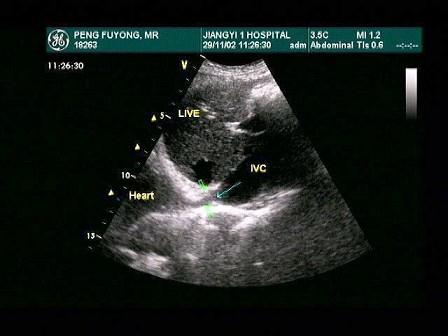

该病例最有可能诊断是?(?)A.布-加综合征B.川崎病C.动脉瘤D.以上都不是E.门静脉高压

问题 该病例最有可能诊断是?(?)

选项 A.布-加综合征 B.川崎病 C.动脉瘤 D.以上都不是 E.门静脉高压

答案 A